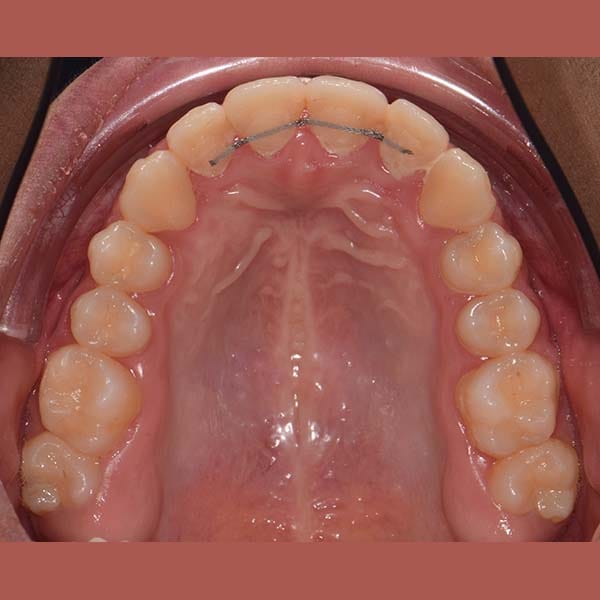

BEFORE

This girl suffered from severe upper jaw stenosis, which negatively affected her smile,

suppressed the beauty of her white teeth when smiling, and also led to a buried upper-right canine in the bone, and a reverse bite in the back teeth.